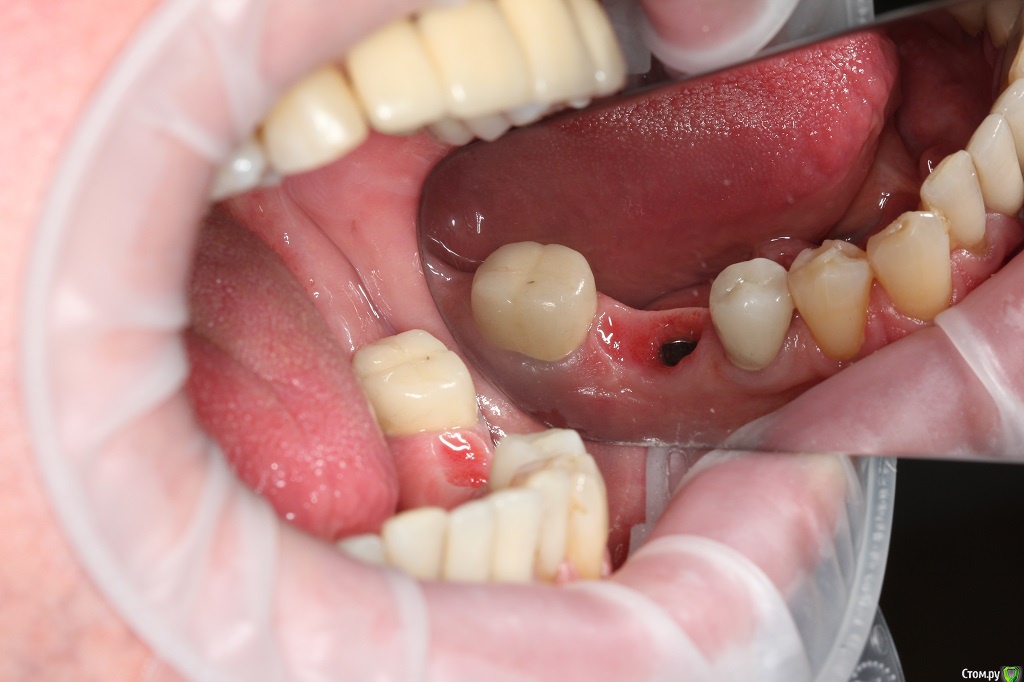

Dr.Sham Опубликовано 11 марта, 2015 Поделиться Опубликовано 11 марта, 2015 (изменено) Год назад в другой клиник пациенту устанавливали имплантаты, вроде одномоментно с удалением.На сегодняшний день жалобы стандартные для такой ситуации (пища застревает, запах изо рта).Коронки демонтировал, увидел "козырьки", нехватку десны, отсутсвие 3 мм от профиля прорезывния до платформы.По КТ, стандартно для селекта - отсутсвие 1,5-2 мм кости по кругу, в полости рта признаков воспаления я не диагностирую, отделяемого нет. На данный момент просто выполировал шейки, чтобы не было козырьков, но пища застревает еще больше, насколько я понимаю. В области 36 - язычно норм, вестибулярно - всего 1 мм, расщепить лоскут вестибулярно и подсадить трансплантат с неба, получим ширину, но не высоту, но как без козырька размоделировать коронку?В области 45 - вестибулярно высота есть, а язычно всего 1 мм, расеплять язычно ищечно и добавлять десну?Если так, то на фдмках вести или как?В области 46 - высота есть по кругу, но нет ЗКПД, какой метод предпочесть, чтобы сохранить уже имеющуюся БШ?Как выходить из ситуации?Кто что думает. Спасибо.Теоретически можно вынуть болты, но интегрированный нобель пару раз выкручивал - выпиливал, удовольствие сомнительное.ПС кстати обратите внимание на цемент на границе коронка-абатмент! Изменено 11 марта, 2015 пользователем Dr.Sham Ссылка на комментарий